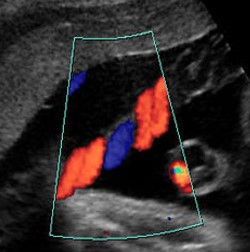

ÚLTIMO ULTRASSOM: Este não tem um momento exato. Vai ser realizado de acordo com a evolução da gravidez, os sintomas da mãe, a espera pelo nascimento... trazendo informações sobre o crescimento do bebê e sobre a circulação na placenta e no cordão umbilical, o chamado ultrassom com Doppler, que vai observar o fluxo de nutrientes e oxigênio nestas regiões.